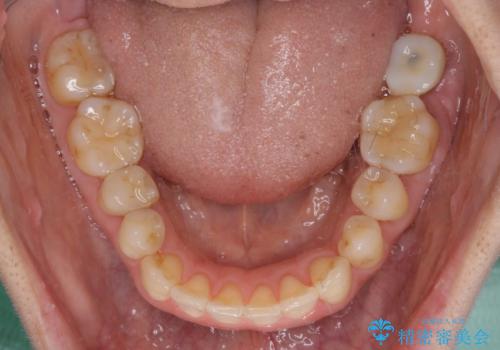

- 上下奥歯の欠損を気にして来院された患者様です。

以前矯正した後戻りにより前歯に叢生が認められたため、矯正治療の提案をしたところ、補綴治療と合わせて矯正治療を行うこととしました。

下顎欠損部はインプラントにて、上顎中間欠損部はブリッジによる補綴治療を行い、他にも気になっている銀歯をセラミックインレーやゴールドインレーにて修復治療を行うこととしました。

後戻りの程度は軽度であったため、インビザライン・ライトを用いて歯列を整えました。

再度後戻りするリスクを最小限に食い止めるため、下顎前歯の舌側を細いワイヤーで固定しました。